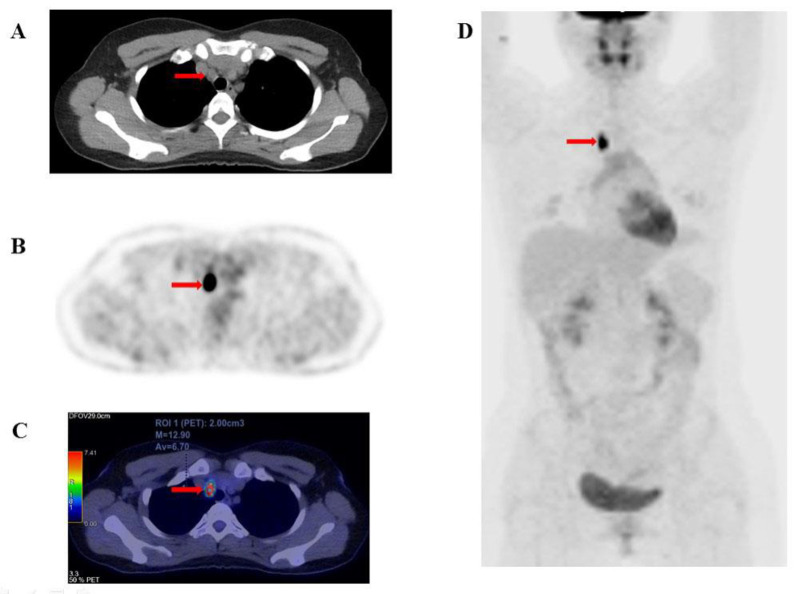

Objectives: This study investigates the relationship between quantitative 18F-FDG PET/CT metabolic parameters and overall survival (OS) in patients with radioiodine-refractory differentiated thyroid cancer (RAI-R DTC).

Methods: We conducted a prospective analysis of 127 patients with RAI-R DTC. Quantitative metabolic parameters including SUVmax, SUVmean, SUVpeak, total metabolic tumor volume (MTV), and total lesion glycolysis (TLG) were assessed in 18F-FDG -avid recurrent or metastatic lesions via 18F-FDG PET/CT imaging. Patients were monitored for disease progression and mortality for at least one-year post PET/CT imaging. Receiver operating characteristic (ROC) curves were used to establish cut-off values for predicting 5-year mortality, while the Kaplan-Meier method estimated the 5-year survival rate. Univariate and multivariate Cox regression analyses identified prognostic factors associated with OS.

Results: The metabolic parameters derived from 18F-FDG PET/CT demonstrated high sensitivity and specificity for predicting 5-year OS. ROC curve analysis established optimal cut-off values for SUVmax (20.27 g/mL), SUVmean (7.46 g/mL), SUVpeak (7.8 g/mL), TLG (45.74 g/mL×cm³), and MTV (5.78 cm3) (AUC: 0.82, 0.78, 0.82, 0.82, and 0.86, respectively; p<0.001). Kaplan-Meier analysis revealed significantly lower OS in patients with higher values of these parameters compared to those with lower ones (survival rates: 42.1% vs. 95.6%, 65.5% vs. 96%, 52.3% vs. 96.3%, 46.5% vs. 97.3%, and 57.3 % vs. 98.3%, respectively; p<0.001). Univariate Cox regression identified SUVmax, SUVmean, SUVpeak, TLG, and MTV as significant predictors of 5-year OS (p<0.05). In multivariate analysis, SUVpeak and MTV emerged as independent predictors of OS.

Conclusion: Quantitative 18F-FDG PET/CT-derived parameters are significant predictors of 5-year OS, exhibiting high sensitivity and specificity. Elevated values of these parameters correlate with increased mortality rates. Our findings suggest that SUVpeak and MTV are independent prognostic factors for 5-year OS in patients with radioiodine-refractory DTC.